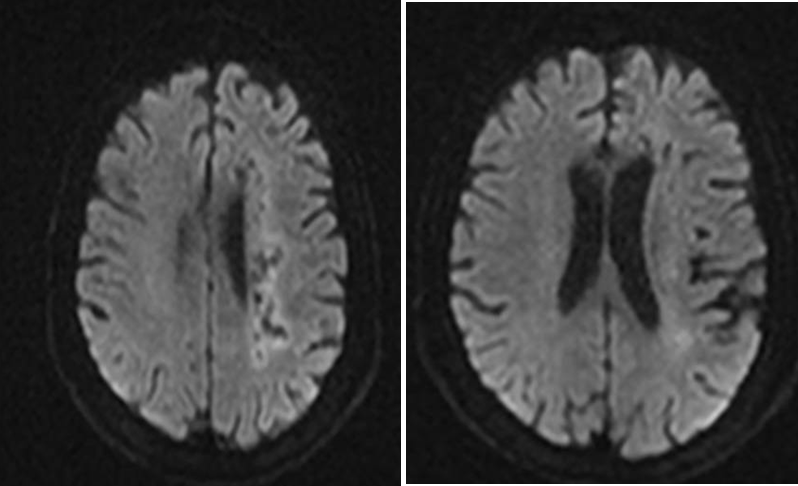

既往影像检查

导丝怎么扩【载药时代 球扩天下】NOVA DES®颅内药物洗脱支架在颈内动脉颅内段重度狭窄中的应用体会二例!_https://www.jmylbn.com_新闻资讯_第3张

DWI

导丝怎么扩【载药时代 球扩天下】NOVA DES®颅内药物洗脱支架在颈内动脉颅内段重度狭窄中的应用体会二例!_https://www.jmylbn.com_新闻资讯_第4张

MRA

重要影像结论:左侧基底节区、放射冠区新发脑梗死;多发脑血管狭窄